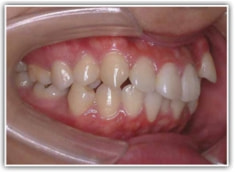

治療前

治療開始時

左右の顎顔面の非対称と、歯の位置の非対称を伴うケースです。

左右の非対称が骨格的にも、歯槽的にも存在し、特に顎の中での上下の歯の位置に、下顎前歯一本分の左右のズレが認められるので、かなり強い非対称といえます。